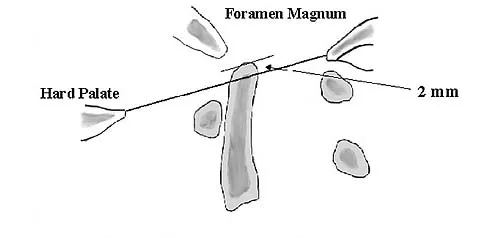

The space available for the cord is an important determinant in neurologic recovery. Recent analysis suggests that the most reliable radiographic predictor for neurologic recovery after surgery in patients with rheumatoid arthritis and paralysis is a preoperative

Explanation